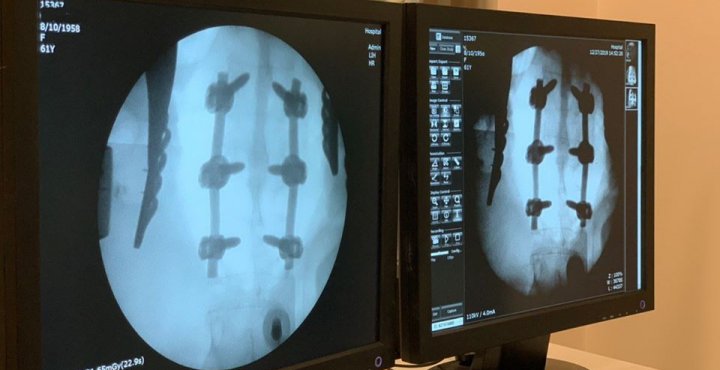

“Було діагностовано компресійний перелом тіла L1 хребця 2 ст. на фоні системного остеопорозу. Нашими нейрохірургами успішно проведена транспедикулярна фіксація хребців (Th12- L1-2)”, – повідомляють на сторінці.

Також додають, що дана операція є золотим стандартом у лікуванні травм хребта. Раніше лікування подібної травми вимагало півроку постільного режиму, наразі вже через два тижні перебування у стаціонарі у задовільному стані жінка пішла додому.